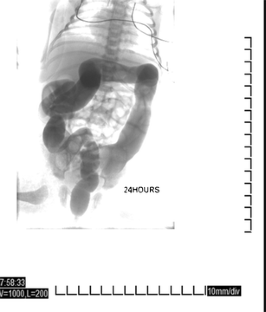

Fig. 2